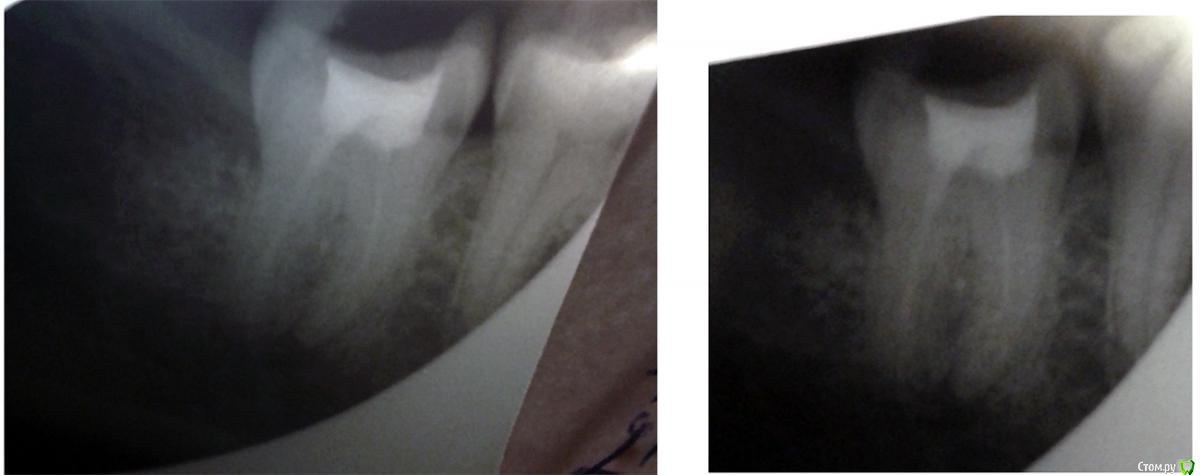

6467t655576 Опубликовано 25 января, 2019 Поделиться Опубликовано 25 января, 2019 (изменено) Здравствуйте.Уже несколько лет беспокоят чередующиеся онемение, боль, непонятные пульсации справа, в районе нижней семерки, хотя дискомфорт нередко охватывает и верхние, и до пятёрок. Удалил все кривые восьмерки - не то. Чуть больше года назад лечил 47, но как-то лучше не стало. Врачи отправляли к неврологу, недавно увидели небольшое воспаление и кололи линкомицин - положительный результат держался меньше недели. На последней оптг узрели кисту, требующую немедленного лечения.Прошу вашего мнения, что видно на снимках, и как с этим бороться (резать десну, "перепроходить" каналы, или правда неврология)?Снимок 47 совсем свежий (дважды, не знаю, какое фото лучше), оптг снимок и фото с монитора в рентгенкабинете около месяца, старая оптг сделана летом. Изменено 25 января, 2019 пользователем 6467t655576 Ссылка на комментарий

kramer Опубликовано 25 января, 2019 Поделиться Опубликовано 25 января, 2019 Мне кажется, здесь картина неврита тройничного нерва и накладывающиеся на него симптомы периодонтита ("киста") зуба 47. Две отдельные проблемы, решать их надо отдельно. 1 Ссылка на комментарий

6467t655576 Опубликовано 25 января, 2019 Автор Поделиться Опубликовано 25 января, 2019 Мне кажется, здесь картина неврита тройничного нерва и накладывающиеся на него симптомы периодонтита ("киста") зуба 47. Две отдельные проблемы, решать их надо отдельно. Спасибо.У меня связалось в одно, т.к. проходит боль - немеет, проходит онемение - болит. Значит периодонтит действительно есть, но кроме "обычной" зубной боли от него ждать нечего? Вскрывать-переделывать? А с корнем 46 (попал в кадр) всё в порядке? Ссылка на комментарий

kramer Опубликовано 25 января, 2019 Поделиться Опубликовано 25 января, 2019 А с корнем 46 (попал в кадр) всё в порядке?не попал Ссылка на комментарий

6467t655576 Опубликовано 25 января, 2019 Автор Поделиться Опубликовано 25 января, 2019 Рентгенолог что-то говорила про шестёрку, может, не так понял. Ссылка на комментарий